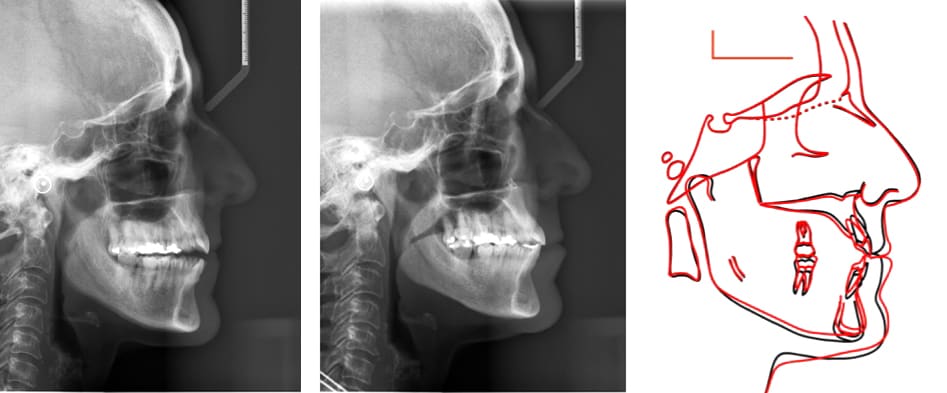

The side view film with the initial cephalometric analysis confirmed the skeletal Class III and open bite discrepancies, the deficit of the upper jaw head development and a slight incisor’s proclination in relation with the tongue posture. (Table 1)

Radiographs were taken before the second phase, showing a huge maxillary expansion of the palatal suture with a good root integrity, a maxillary advancement of point A in relation to SN (SNA=4,7°) but an aggravation of the skeletal open bite (Go-Gn/SN=37,5°) and occlusal plane to SN (17,5°). (Table 2)

The final cephalometric analysis and the structural superimpositions show an incredible anterior mandibular auto-rotation with a counter clockwise movement of the face, the mandibular plane and the occlusal plane leading to a skeletal and bite closure.

Within the sagittal skeletal patterns, the slight proclination of the incisors after treatment helped to get an ideal overjet/overbite and an improvement of the profile. (Table 4-2)